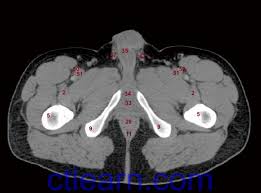

The video covers the most. Hint you are sitting on it right now. The pelvic girdle consists of two symmetrical halves. The muscles of the pelvis form its floor. Hepatocellular carcinoma or liver cancer. Furthermore, the pelvis protects the pelvic and abdominopelvic viscera. (2) the levator ani and the coccygeus, which together form the pelvic diaphragm and are. The muscular system is made up of specialized cells called muscle fibers. • describe the bony anatomy of the pelvic floor • describe the skeletal muscle of the pelvic floor • discuss the arterial supply to pelvis. Abdominal and pelvic anatomy encompasses the anatomy of all structures of the abdominal and pelvic cavities. 3 enumerate the muscles of true pelvis. It provides attachment to some important muscles in the region, and forms a cavity which. 13 what portion of the bony pelvis is the arrow pointing to?

This mri male pelvis axial cross sectional anatomy tool is absolutely free to use. Muscles, connected to bones or internal organs and blood vessels, are in charge for movement. Learn about anatomy muscles pelvis with free interactive flashcards. Pelvic examinations are common in clinical cases of obstetrics and gynecology the bony pelvis can be divided and viewed into 2 parts: Ischial tuberosity which flexor of the knee attaches here?

Ct anatomy of the pelvis.

(1) the obturator internus and the piriformis, which are muscles of the lower extremity, and will be described with these (pages 476 and 477); This mri male pelvis axial cross sectional anatomy tool is absolutely free to use. Additional 3d anatomical images are available on the end of module, for a better understanding of gross anatomy of the dog, displaying 3d volume rendering of bones, splanchnology (liver, spleen anatomy of the male canine abdomen and pelvis on ct imaging: 0835 lotze anatomy of the pelvic floor. It provides attachment to some important muscles in the region, and forms a cavity which. Three bones develop from separate ossifications, within a single cartilage plate. The female reproductive tract 239. This mri male pelvis axial cross sectional anatomy tool is absolutely free to use. Ischial tuberosity which flexor of the knee attaches here? ƒ organs and structures of the female pelvis. The pelvis is a basin shaped bony structure formed by the combination of two pelvic bones (hip bones or innominate bones) and the sacrum. Ct anatomy of the pelvis. It is strengthened and supported by several joints and ligaments.

Ischial tuberosity which flexor of the knee attaches here? anatomy muscles pelvis. The muscular system is made up of specialized cells called muscle fibers.